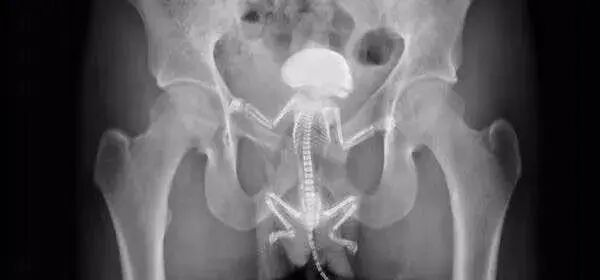

有大爷睡觉时把宠物松鼠“收编”进菊花,醒来发现人鼠难分,急诊医生边抢救边怀疑人生;